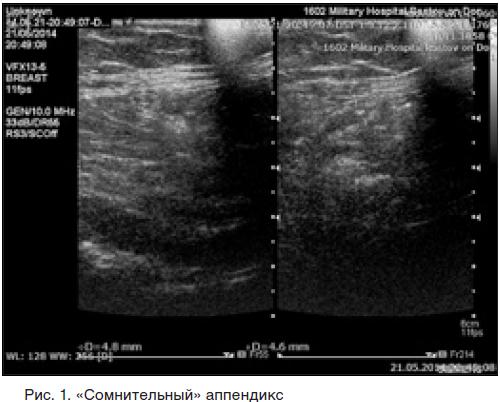

Узи выявит аппендицит 117 фотографий